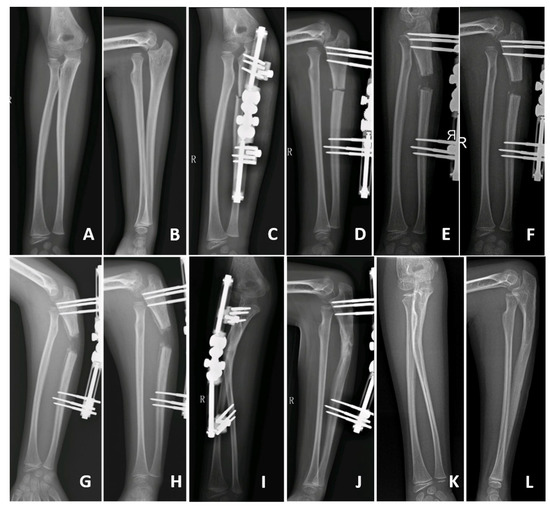

- Lengthening distance of the ulna (DU): the distance, in millimetres (mm), between the proximal and distal fragments of the fractured ulna (Figure 3); and

- Angulation of the ulna (AU): the angle, in degrees, between the line passing at the level of posterior cortex of the proximal and the distal fragment of the fractured ulna (Figure 3);